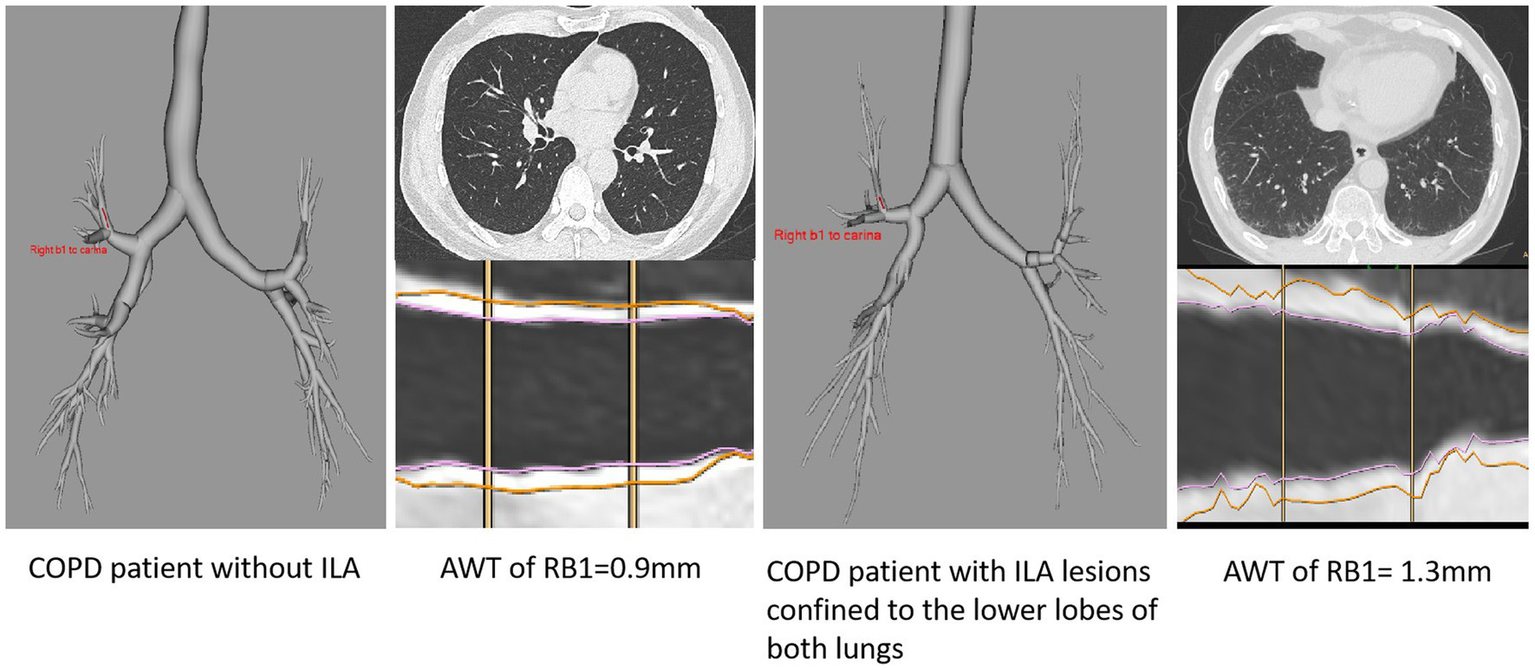

Furthermore, the findings of this association could be due to the ILA lesions only changing the adjacent airways, we excluded this possibility by selecting patients with ILA whose lesions were confined to the lower lobes of both lungs, and quantitative CT measurements of these patients (including AWT of RB1, RB4, LB1+2, the average of AWT of RB1, RB4, LB1+2, the average WA% of RB1, RB4, LB1+2) compared to patients with no ILA were analyzed (Table 4; Figure 4), We did not include Pi10 as the airway measure because it is a composite indicator. Similar higher measurements of AWT were noted in COPD patients whose ILA lesions were confined to the lower lobes, the results were observed in both univariate and multivariate analyses, which were adjusted for important covariates. The measures of AWT of RB1, the average AWT and WA% of these three segmental airways in COPD patients with ILA were significantly higher than those with no ILA. In addition, similar higher AWT measurements of RB4 and LB1+2 were also noted in COPD patients with ILA compared with those with no ILA, but no significant differences were observed between the two groups. In the adjusted analyses, compared to COPD patients without ILA, the average AWT and WA% measures of these three segmental airways were 0.189 mm (p = 0.001) and 3.897% (p = 0.013) higher in those with ILA, and higher AWT measures of RB1 with the difference of 0.287 mm (p < 0.001) in those with ILA.

Figure 4

Entire airway tree slice of RB1 bronchi of COPD patients with and without ILA.